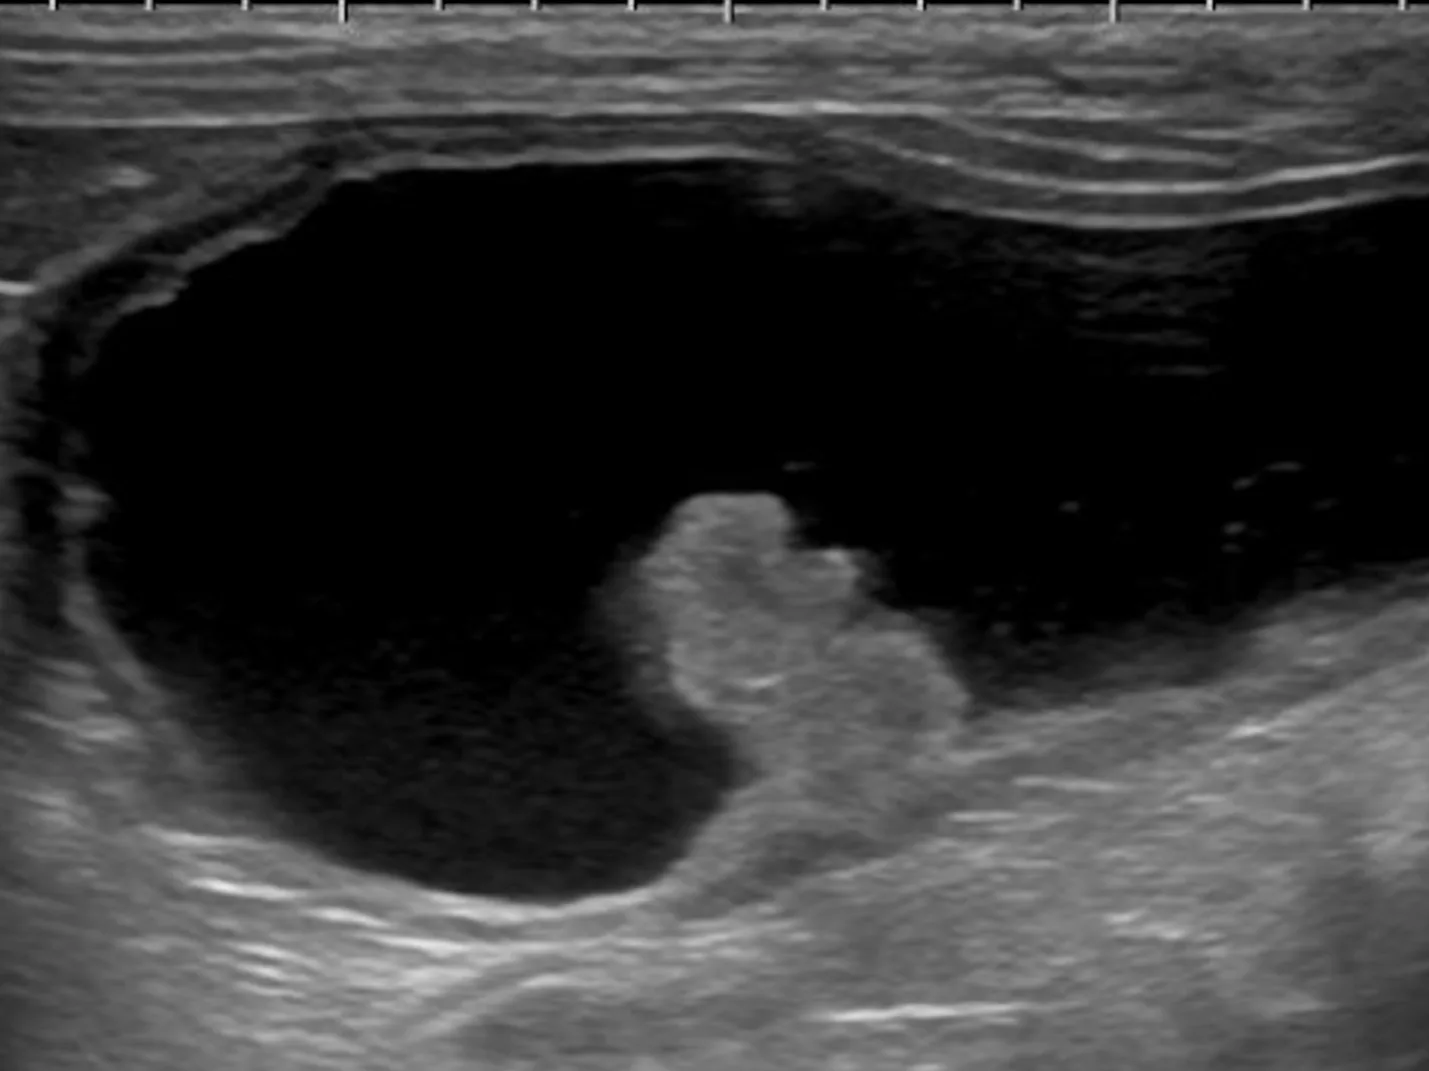

腹部超音波検査

膀胱腫瘤、腎臓、腰下リンパ節群を中心に評価します。